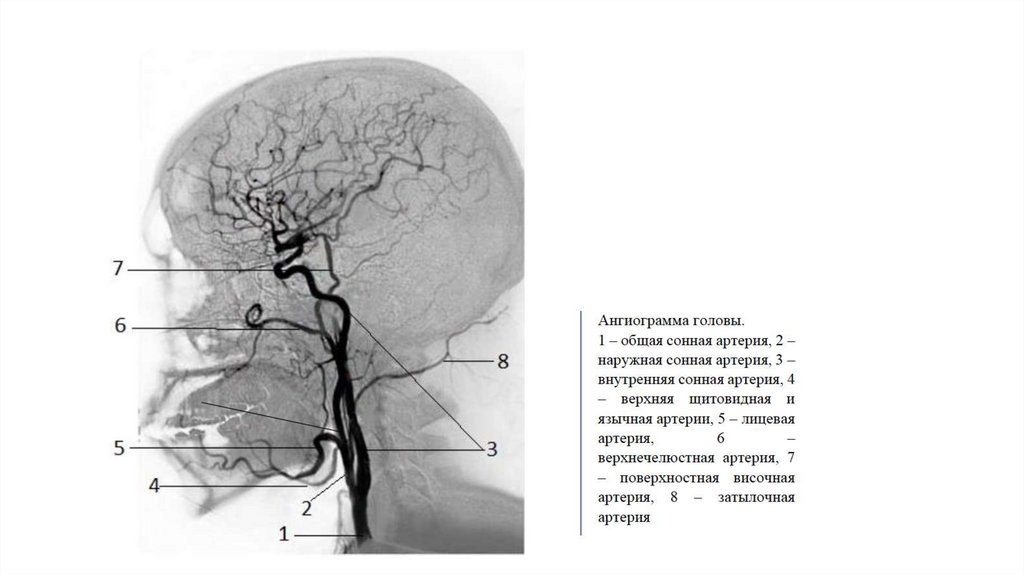

• В своем начальном участке лежит

позади легочного ствола(4).